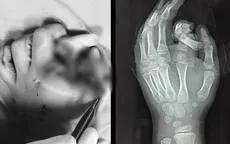

Bé 6 tuổi đứt rời ngón tay khi cho tay vào máy giặt đang hoạt động

VTV.vn - Thông tin từ Bệnh viện Đa khoa Xanh Pôn (Hà Nội), bệnh viện vừa tiếp nhận 1 bệnh nhi 6 tuổi, ở Hà Nội bị tai nạn sinh hoạt khi cho tay vào máy giặt đang hoạt động.